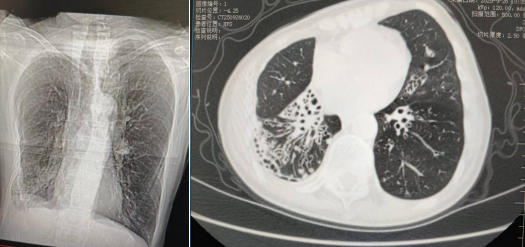

患者胸部CT影像

患者女性,67岁,反复咳嗽、咳痰30余年,每天约上百毫升痰量,日常生活及睡眠受到极大困扰,近日以“咳嗽、咳痰再发加重1个月”为主诉,就诊于呼吸与危重症医学科。胸部CT检查显示:胸廓塌陷、气管向右侧偏移,双肺支气管可见多发囊状扩张、管壁增厚。